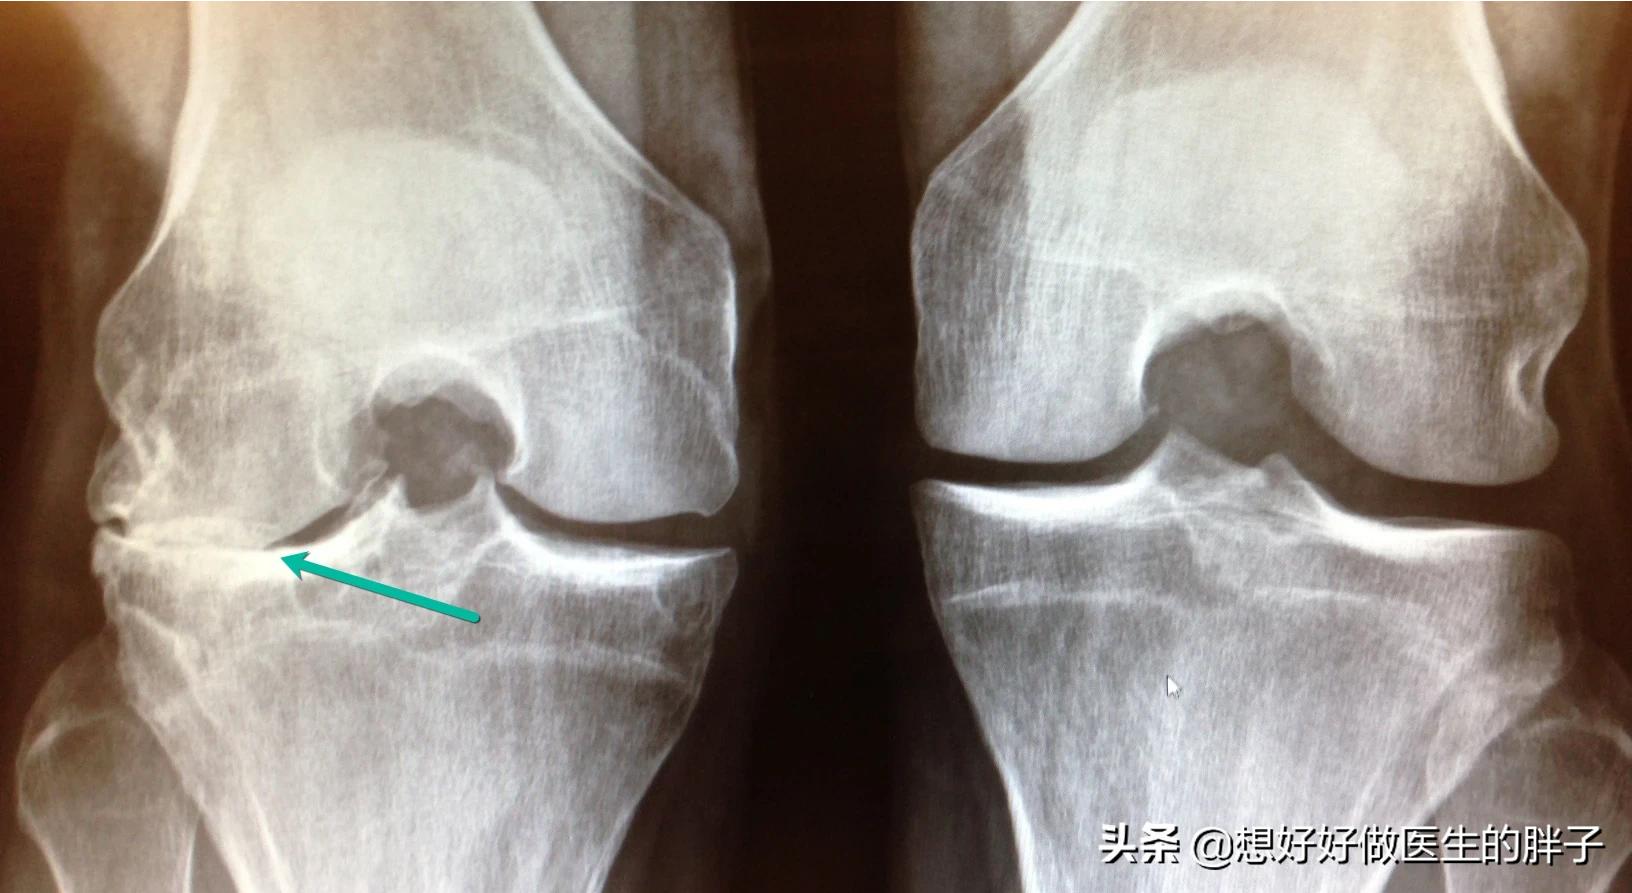

关节腔内的软骨发生磨损以后,关节运动的时候就不再那么光滑了,在早期并不会有特别的症状,有一些患者在劳累时可能会出现关节的疼痛,或者是在天气变化的时候有关节的不适,随着对软骨磨损的加大,软骨会磨得越来越薄,那么关节内承受的压力也会越来越大,关节为了更好的增加负重的面积,为了维持关节的稳定,就会生成一个我们大家都害怕的结构骨赘,那就是骨刺,老百姓习惯地称之为骨质增生。

随着病情的进一步进展,软骨会磨损的越来越薄,有的时候关节间隙的软骨会磨的彻底消失掉,就会发生关节间隙的狭窄。患者明显出现关节功能的障碍、疼痛,有一些患者继发滑膜炎以后,会出现反复的关节积液。

所以骨关节炎的特点是:骨赘的形成以及关节间隙的狭窄!